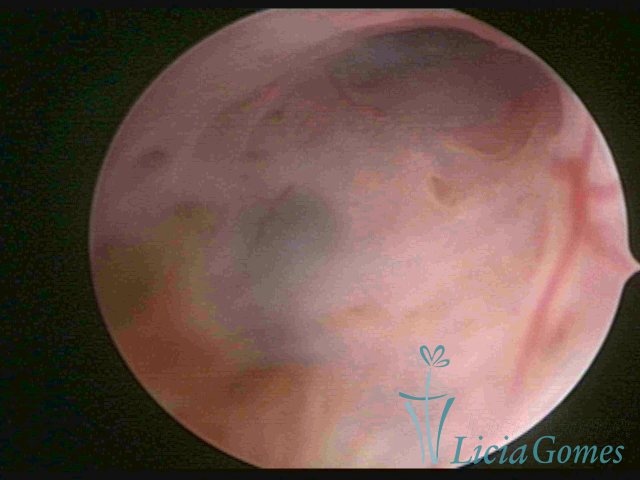

ADENOMIOSE

É a presença de tecido endometrial na camada muscular do útero

A vídeo-histeroscopia permite diagnosticar às lesões próximas às camadas miometriais superficiais, próximo ao endométrio visualizando lesões de coloração violácea, circunscritas, ou acastanhadas com conteúdo achocolatado.